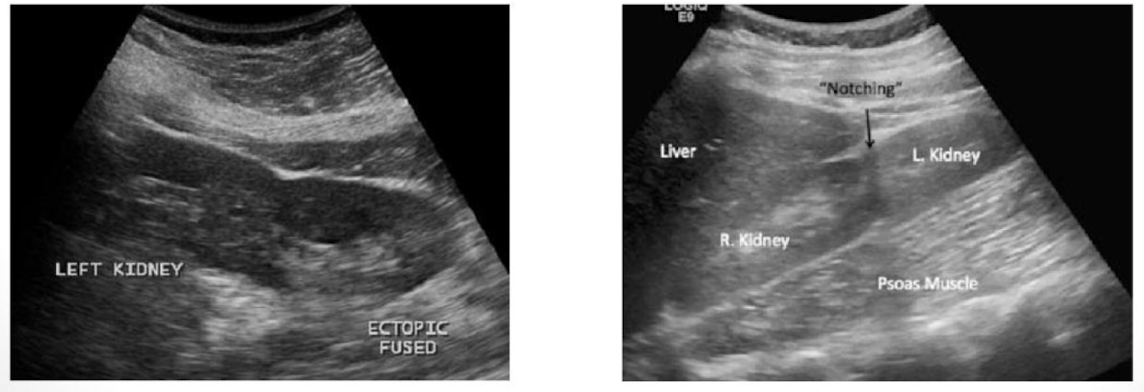

This type of congenital variant occurs when there is fusion of the kidneys.typically the fusion is of the lower poles

Horseshoe kidney

Which type of analomy is shown in this image→ ?

both kidneys are located on one side of the body. What type of ectopic kidney is this:

Ectopic kidney: cross fused